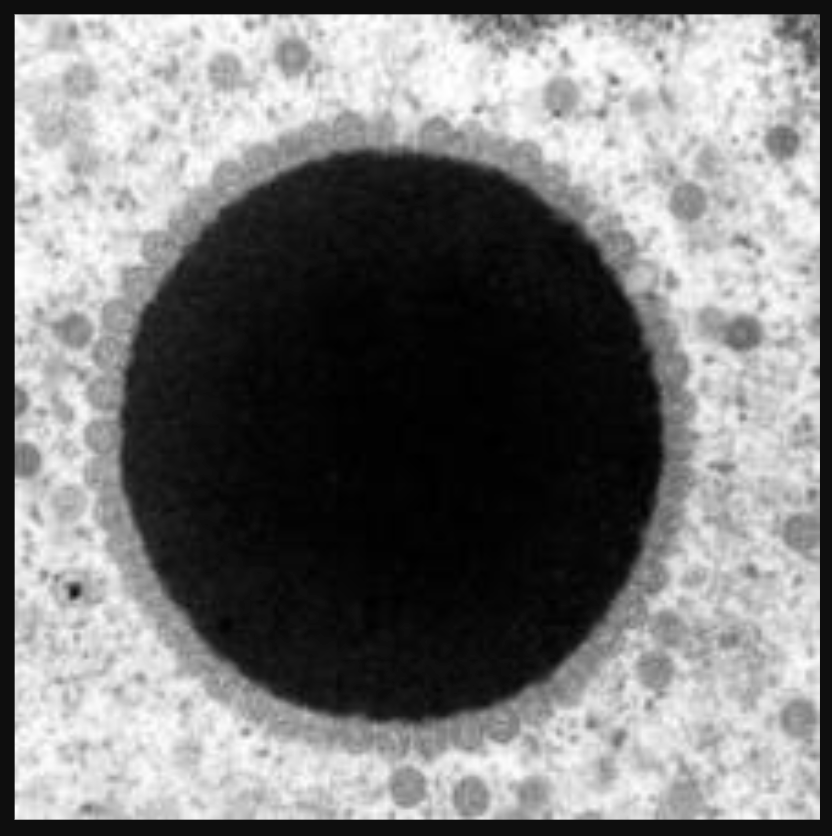

Figure 5. An electron microscopic image of chelonid herpesvirus 5

Photo: usgs.gov/media/images /chelonid-herpesvirus-5-replication